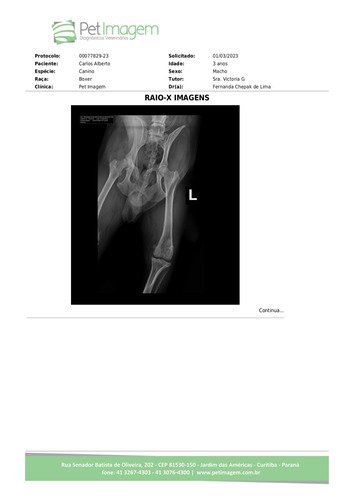

Ele rompeu um ligamento do joelho direito, precisará de cirurgia ortopédica. Na mesma perna também possui um lipoma que se exteriorizou, causando uma ferida que necessita de cuidado constante, pois eventualmente sangra bastante. Então ele precisa de duas cirurgias. Uma para reparar o ligamento do joelho, – esta é a mais cara e a mais necessária, a dor é tamanha que ele não consegue apoiar a pata ao chão, e devido a esse problema, não pode mais passear, para não complicar ainda mais a lesão, causando coceira devido ao estresse do repouso, além disso, ele chora dia e noite devido a dor! – e a outra cirurgia, para retirar o lipoma, este que aparece nas fotos. Também há fotografia do resultado do exame de “raio-x” que demonstra a necessidade de cirurgia de ligamento cruzado do joelho, e a constatação do lipoma, que tanto o incomoda.